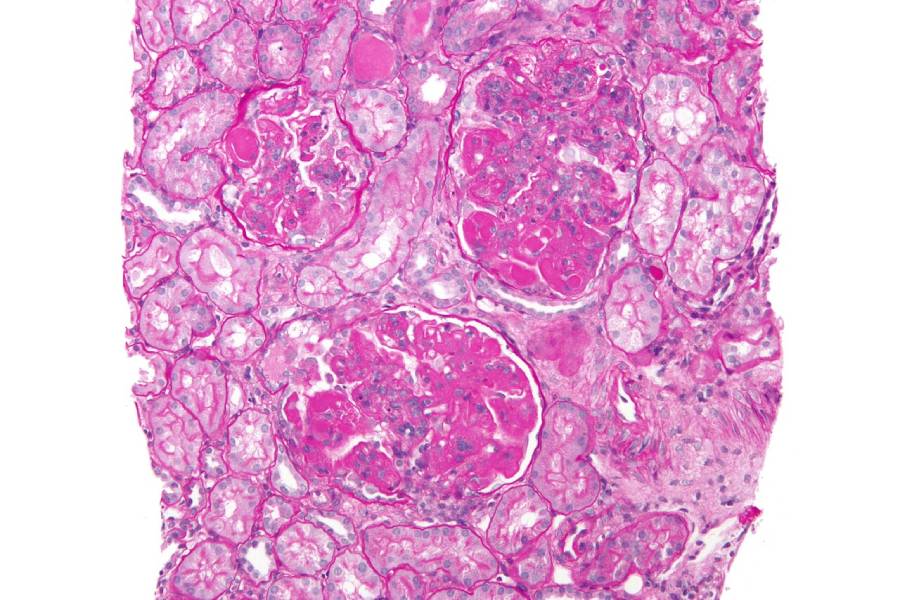

Микрография диффузного пролиферативного волчаночного нефрита Фото: Nephron / wikipedia.org